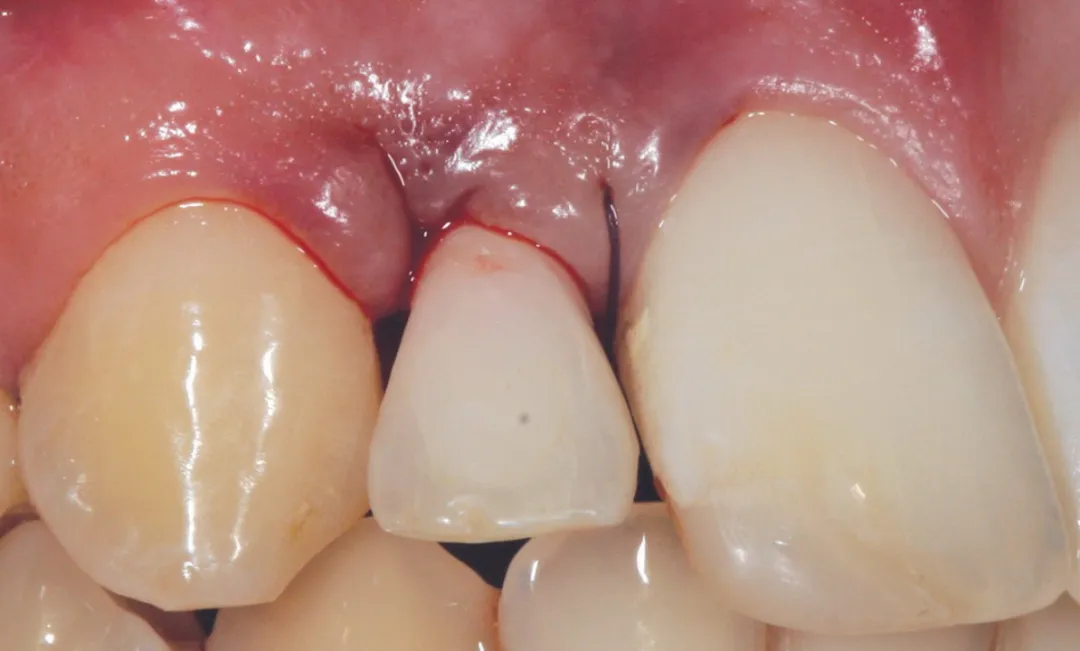

2 号病例 - Patrick EXBRAYAT 医生(图 21 至 35)

22 岁患者,23 异位,行正颌外科种植术后 22 出现严重根吸收。

图 29 :临时冠粘接后,腭面观。

图 30 :临时冠粘接后,唇面观。